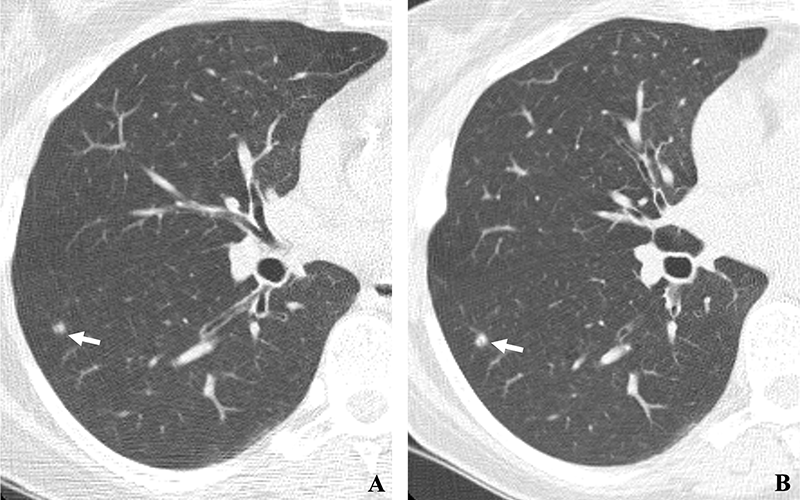

(A, B) Two annual repeat low-dose CT scans in a woman who was 60 years old at baseline enrollment in 1999. At baseline enrollment, she was currently smoking and had a 30-pack-year smoking history. No nodules were identified on baseline low-dose CT scans. On the sixth annual low-dose CT scan (B), a right lower lobe solid nodule (arrow) measuring 4.5 mm in maximum diameter was identified. The nodule could be identified in retrospect on the prior annual CT scan (arrow in A), when it measured 2.0 mm in maximum diameter. Estimated tumor volume doubling time was 161 days. Lobectomy was performed 2 months later, and diagnosis of stage 1aN0M0 moderately differentiated adenocarcinoma measuring 6.0 mm in maximum diameter was made. Expert pathologic panel review (22) of the pathologic specimen updated the diagnosis to adenocarcinoma with mixed subtype (80% acinar, 20% bronchoalveolar carcinoma components) with 5 mm of invasion.